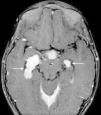

La histiocitosis de células de Langerhans (HCL) es una enfermedad rara caracterizada por la acumulación en los tejidos de células dendríticas anómalas similares a las células de Langerhans. La presentación clínica varía desde la aparición de una lesión ósea única hasta la afectación multisistémica. La implicación del sistema nervioso central (SNC), manifestada como diabetes insípida secundaria a afectación hipofisaria, es conocida desde la descripción original de la enfermedad. En la actualidad, se diferencian 2 tipos de lesiones del SNC: las lesiones seudotumorales, con infiltración por las células de Langerhans, cuya manifestación más frecuente es la infiltración hipofisaria, y otras, de más reciente descripción, las lesiones neurodegenerativas del SNC, asociadas a deterioro neurológico, que constituyen una complicación de la enfermedad de causa discutida. Nuestro objetivo es describir las manifestaciones radiológicas de la HCL en el SNC en los pacientes pediátricos.

Langerhans cell histiocytosis (LCH) is a rare disease characterized by the accumulation within tissues of anomalous dendritic cells similar to Langerhans cells. The clinical presentation varies, ranging from the appearance of a single bone lesion to multisystemic involvement. Central nervous system (CNS) involvement, manifesting as diabetes insipidus secondary to pituitary involvement, has been known since the original description of the disease. Two types of CNS lesions are currently differentiated. The first, pseudotumoral lesions with infiltration by Langerhans cells, most commonly manifests as pituitary infiltration. The second, described more recently, consists of neurodegenerative lesions of the CNS associated with neurologic deterioration. This second type of lesion constitutes a complication of the disease; however, there is no consensus about the cause of this complication. Our objective was to describe the radiologic manifestations of LCH in the CNS in pediatric patients.